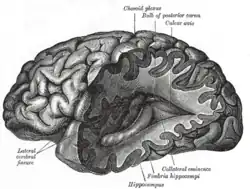

The nervous tissue found in the brain, spinal cord, and periphery comprises an extraordinarily complex biological system that largely defines many of the unique traits of individuals. As with any highly complex system, however, even small perturbations to its environment can lead to significant functional disruptions. Properties leading to the susceptibility of nervous tissue include a high surface area of neurons, a high lipid content which retains lipophilic toxins, high blood flow to the brain inducing increased effective toxin exposure, and the persistence of neurons through an individual's lifetime, leading to compounding of damages.[21] As a result, the nervous system has a number of mechanisms designed to protect it from internal and external assaults, including the blood brain barrier.

The blood-brain barrier (BBB) is one critical example of protection which prevents toxins and other adverse compounds from reaching the brain.[22] As the brain requires nutrient entry and waste removal, it is perfused by blood flow. Blood can carry a number of ingested toxins, however, which would induce significant neuron death if they reach nervous tissue. Thus, protective cells termed astrocytes surround the capillaries in the brain and absorb nutrients from the blood and subsequently transport them to the neurons, effectively isolating the brain from a number of potential chemical insults.[22]

This barrier creates a tight hydrophobic layer around the capillaries in the brain, inhibiting the transport of large or hydrophilic compounds. In addition to the BBB, the choroid plexus provides a layer of protection against toxin absorption in the brain. The choroid plexuses are vascularized layers of tissue found in the third, fourth, and lateral ventricles of the brain, which through the function of their ependymal cells, are responsible for the synthesis of cerebrospinal fluid (CSF).[23] Importantly, through selective passage of ions and nutrients and trapping heavy metals such as lead, the choroid plexuses maintain a strictly regulated environment which contains the brain and spinal cord.[22][23]